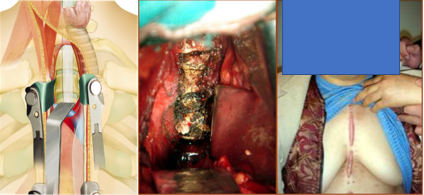

术中照片或手术录像

前入路完整切除OPLL (T1-T2)

颈7~胸2前路固定

脑脊液漏的处理: